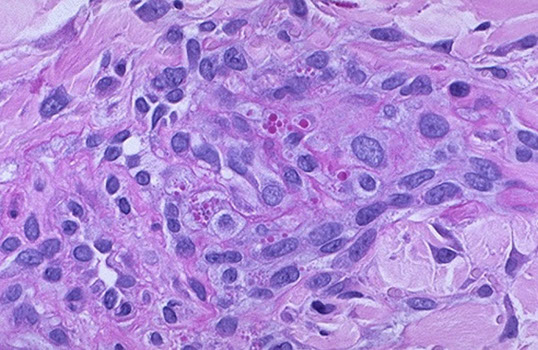

Granulomatosis with polyangiitis (GPA)

- formely (Wegener's granulomatosis)

Triad of upper respiratory tract, lung, kidney

- focal necrotizing vasculitis, necrotizing granulomas in the lung and upper airway, necrotizing glomerulonephritis

Sx: hemoptysis, nasal septum perforation, chronic sinusitis

*** the C's: Cavitary lesions, Crescentic GN, C-nose, C-anca, Cyclophosphamide, Corticosteroids ***

Micro: Fibrinoid necrosis c early neutrophils followed by macros and granuloma c giant cells

- see focal segmental necrotizing glomerulonephritis, pauci-immune type, in kidneys

- palisading necrotizing granuloma with neutrophils (stellate abscesses)

- epidermis necrotic or ulcerated

- necrosis is blue bc comes from neutrophilic microabscesses

Triad: 1) mixed inflam c GCs; 2) geographic necrosis, 3) vasculitis

Labs: (+) Anti-proteinase 3 (PR3-ANCA) by ELISA [formerly C-ANCA]

*** 3 = W ***

cANCA (+) in >90% of cases [5-20% pANCA (+)]

- Confirm Wegener's c ELISA for anti-proteinase 3 !!!

- urinalysis: hematuria and red cell casts

Imaging: large nodular densities

Tx: Cyclophosphamide, Corticosteroids

Geographic necrosis in Wegener's